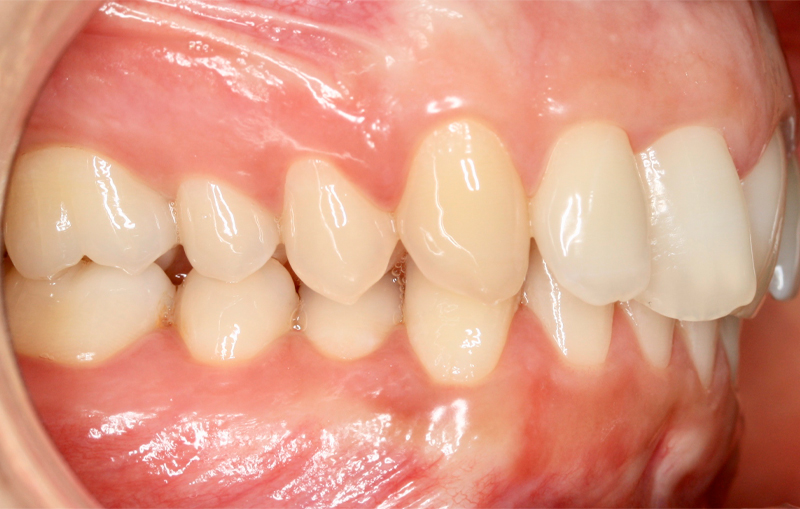

Fotografe a sua Boca de acordo com os exemplos abaixo demonstrados